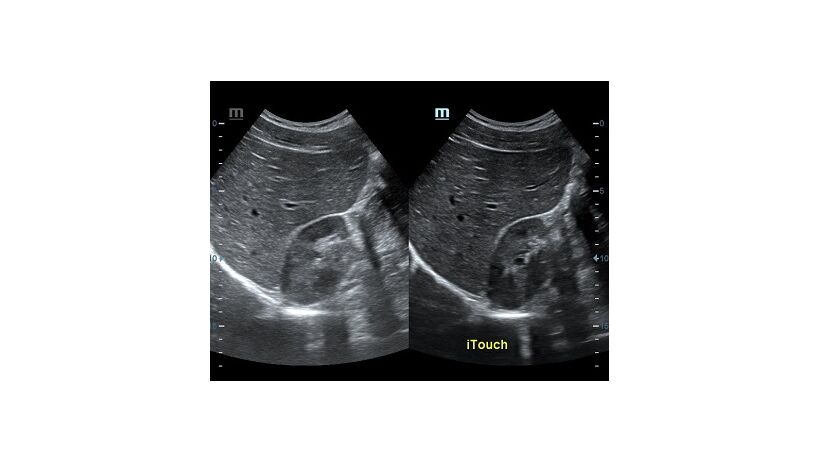

Оптимизация изображения происходит и за счет постобработки. Наиболее часто используемый инструмент - общее усиление (Gain). Усиление делает изображение «ярче», но чем сильнее усиление, тем меньше различия между структурами. Также используются усиление по времени (TGC) и усиление по длине (LGC), которые позволяют изменять отображение на экране послойно, позволяя подсветить гипоэхогенные участки, или, наоборот, снизить визуально эхогенность слишком ярких моментов. Данный вид оптимизации требует много времени, для упрощения работы доктора на приборах Mindray внедрена система автоматической оптимизации - iTouch.